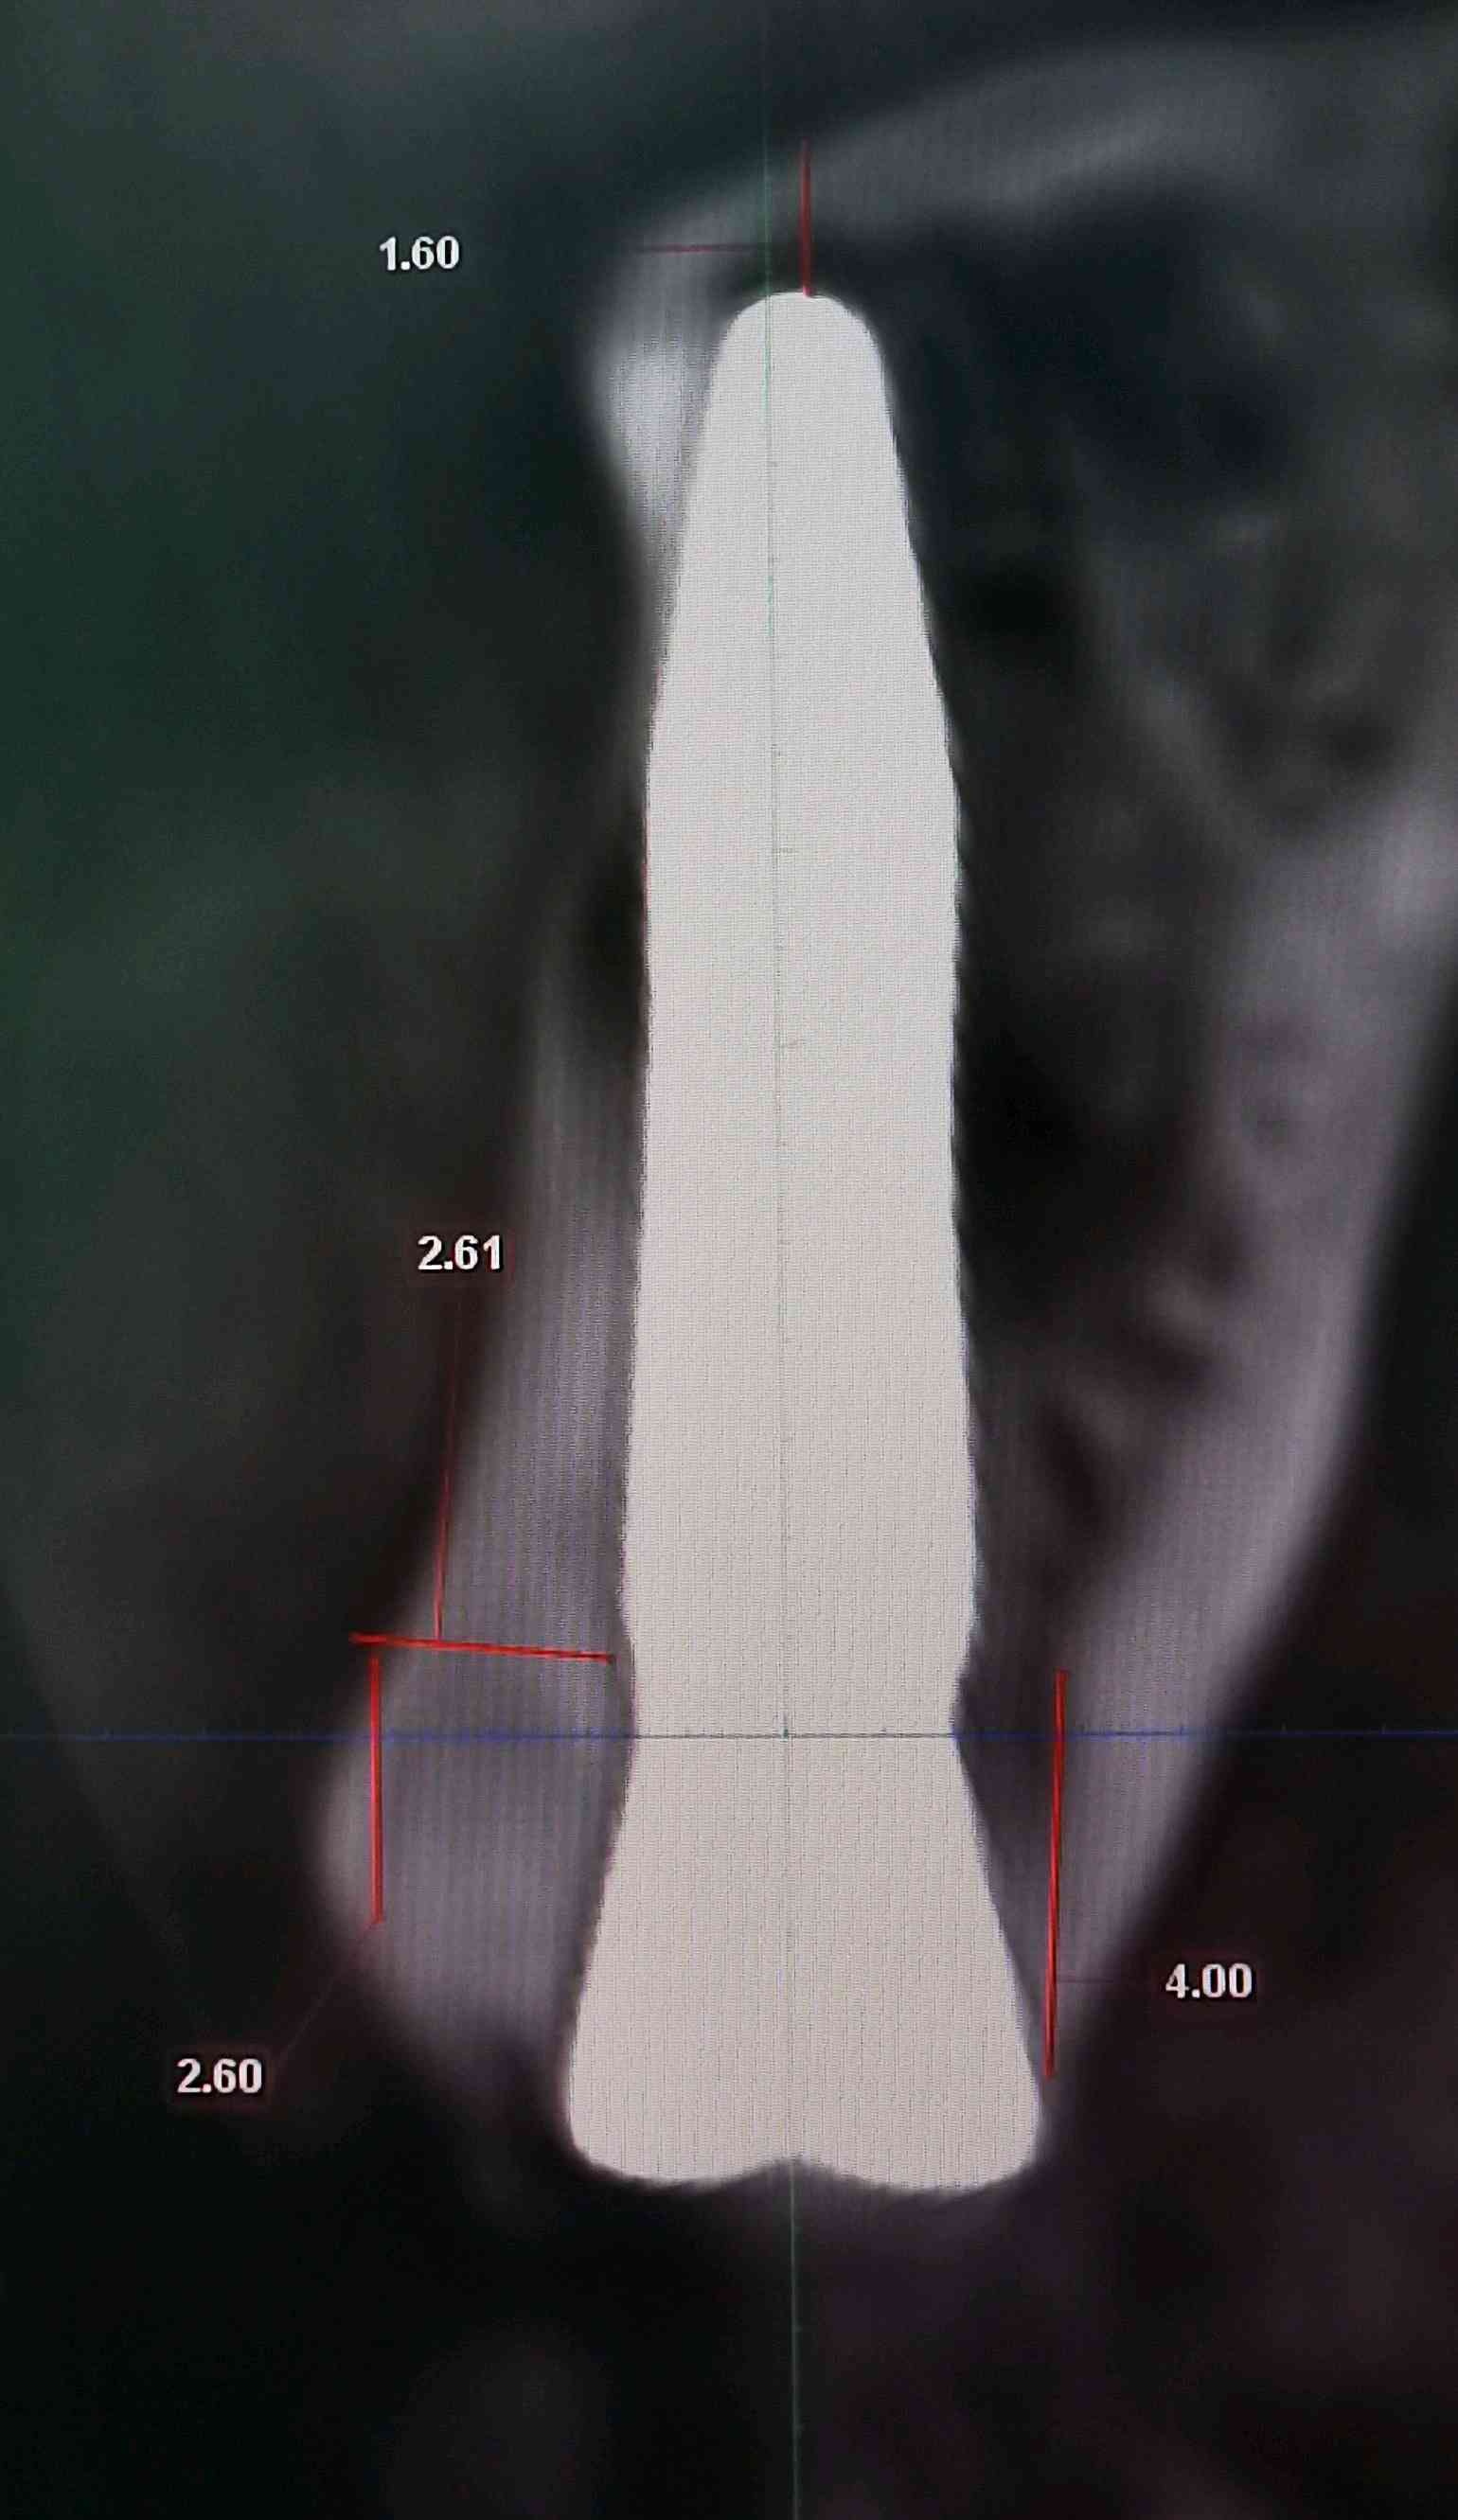

a.术前准备拍摄颌面部 CBCT ,评估骨质骨量,设计种植体植入的位置、轴向、直径和长度。

c、即刻植入根据拔牙窝的位置方向和颌骨的解剖形态,将钻头方向贴着腭侧骨板,采用逐级备洞的方法制备种植窝,植入适当长度和直径的种植体。即刻修复如种植体初期稳定性≥35N/ cm ,可行即刻修复。术中行数字化无痛印模,送工厂行高精度义齿制作,1周内复诊,行义齿戴入,所有即刻修复体均调整至正中、前伸和侧方咬合均无接触。根据种植愈合情况,即刻修复3-6个月后再行永久修复

案例左上2号根尖囊肿

根尖黄豆大小囊肿伴根纵折

3.5倍显微镜下拔牙,刮囊肿,植入ITI 种植体。